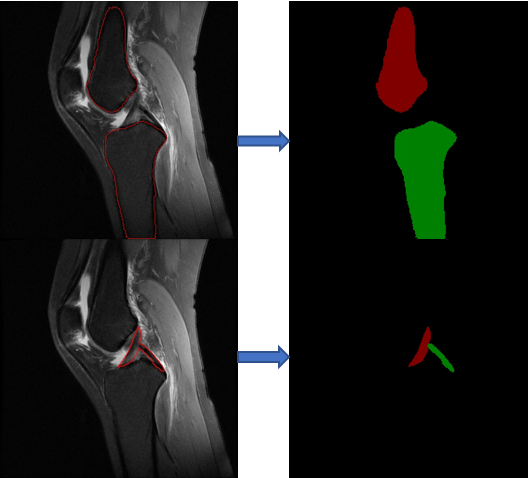

Cruciate ligament injury is very common in daily life. At present, many ligament reconstruction operations are based on the experience of doctors, and errors are inevitable. Extraction and reconstruction of cruciate ligament insertion is very important, which can help doctors to analyze and predict before surgery, and improve the success rate of surgery.